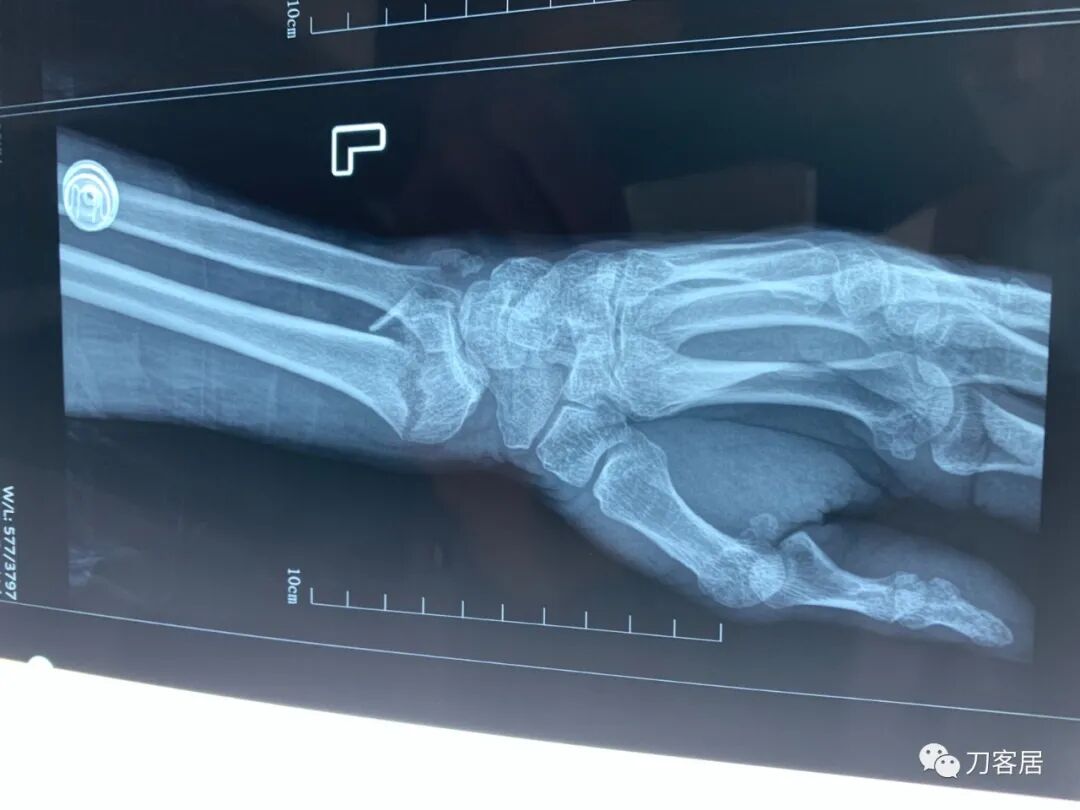

下面是这个6岁孩子,尺桡骨远端双骨折的术前及术后片子和外观照片。

2.  这个骨折处理起来也很简单,单纯的打石膏托或者中医的小夹板,或者正规的包括腕关节和肘关节的管型石膏外固定4周即可治愈该骨折。实在不行,如果这个孩子比较听话,不太调皮的话,用一本书,一个三角巾悬吊固定4周,都可以治愈该骨折。但是给这个患者用外固定架做了手术,而且桡骨远端的几颗克氏针距离骨折线太近,其中一枚克氏针进入到骨折间隙内。从这个术中图片来看,术者的外固定手术技术也有待于进一步的提高。毕竟术者应该还很年轻。从X线片来看,前臂及手的尺侧有不透光影,应该还使用了外固定石膏绷带托,而且我猜测应该是高分子的石膏绷带托,这个是纯属猜测,不一定是对的,不过如何解释前臂尺侧的不透光影呢?如果真是用了石膏绷带外固定的话,那为啥要做手术呢?外固定架术后就不该再用石膏绷带托辅助了。